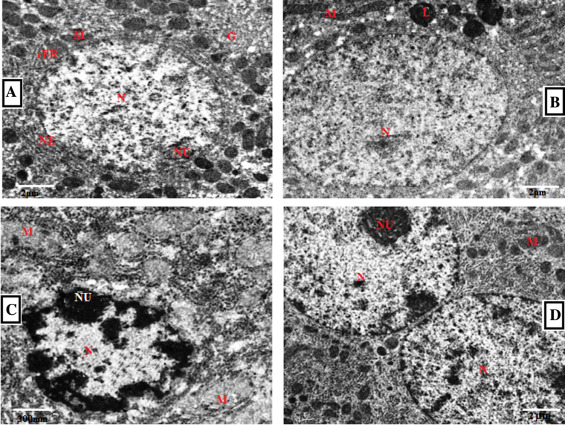

Fig. 14 , reveals the electron microscopic examination of the control and experimental rat livers. The hepatocytes of control group have normal structures with well-distributed cytoplasm. The nucleus was normal with other organelles (Fig. 14 A). In Cd-treated group, hepatocytes showed altered nucleus and degenerated mitochondria. Also, flattened nuclei, flattened microvilli with unevenly distributed glycogen and a number of lipid droplets were observed (Fig. 14 C). Cd and GSP pretreated group revealed that the nucleus appeared normal with free ribosome and regular-shaped nuclei. Binucleated hepatocytes were abundant and evenly distributed heterochromatin and euchromatin were also seen (Fig. 14 D). In GSP alone-treated group hepatocytes with normal mitochondria, rough endoplasmic reticulum was observed (Fig. 14 B).

Electron micrographs of liver in control and experimental rats. (A) Control ...

Fig. 14.

Electron micrographs of liver in control and experimental rats. (A) Control group showing nucleus (N), nucleolus (NU), nuclear envelop (NE), Golgi (G), mitochondria (M) and rough endoplasmic reticulum (rER) with few fat droplets and well-distributed cytoplasm. The nucleus was normal with other organelles (B) GSP alone-treated group shows hepatocytes with normal mitochondria, rough endoplasmic reticulum, nucleus with few chromatin and lysosomes. Hepatocytes with large nucleus, evenly distributed chromatin were also seen. (C) Cd treated group showing pyknotic nucleus with abnormal envelop, degenerated mitochondria, flattened microvilli with unevenly distributed glycogen and a number of lipid droplets were observed (D) Cd and GSP-pretreated group showing Binucleated cell with normal nucleus, mitochondria, rough endoplasmic reticulum with dense chromatin. (5000×).